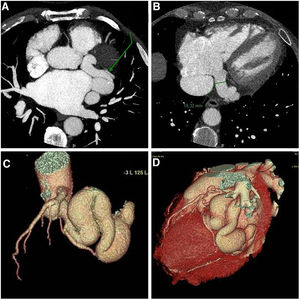

- Entre la fibrilación auricular y la ablación: un hallazgo inesperado

- Ismael Arco Adamuz, Torcuato Garrido-Arroquia Jurado, Rocío García Orta

- Rev Esp Cardiol. 2025;78:1018-9